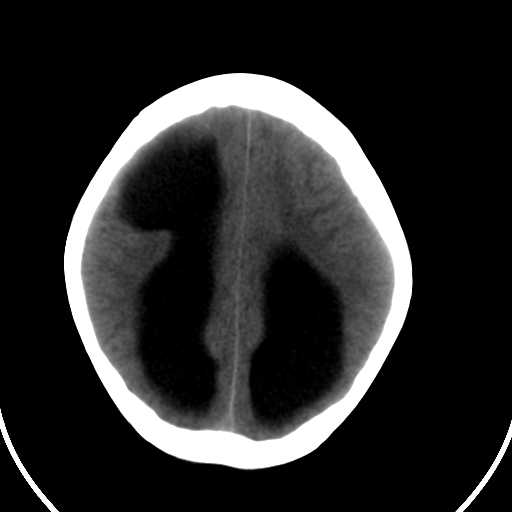

男,11岁

右额叶单发近圆形低密度影,周边光滑,与侧脑室相通,考虑为孔洞脑并阻塞性脑积水。

右额叶内见一边界清楚,脑脊液密度的囊腔,无灰质内衬,并与脑室相通,四室以上脑室系统高度扩张。诊断:先天性脑穿通畸形伴梗阻性脑积水

需要与脑裂畸形鉴别:可见单侧或双侧衬有皮层的脑裂伸入额顶叶的白质内并与脑室相通

脑穿通畸形并梗阻性脑积水.

脑穿通畸形囊肿脑积水